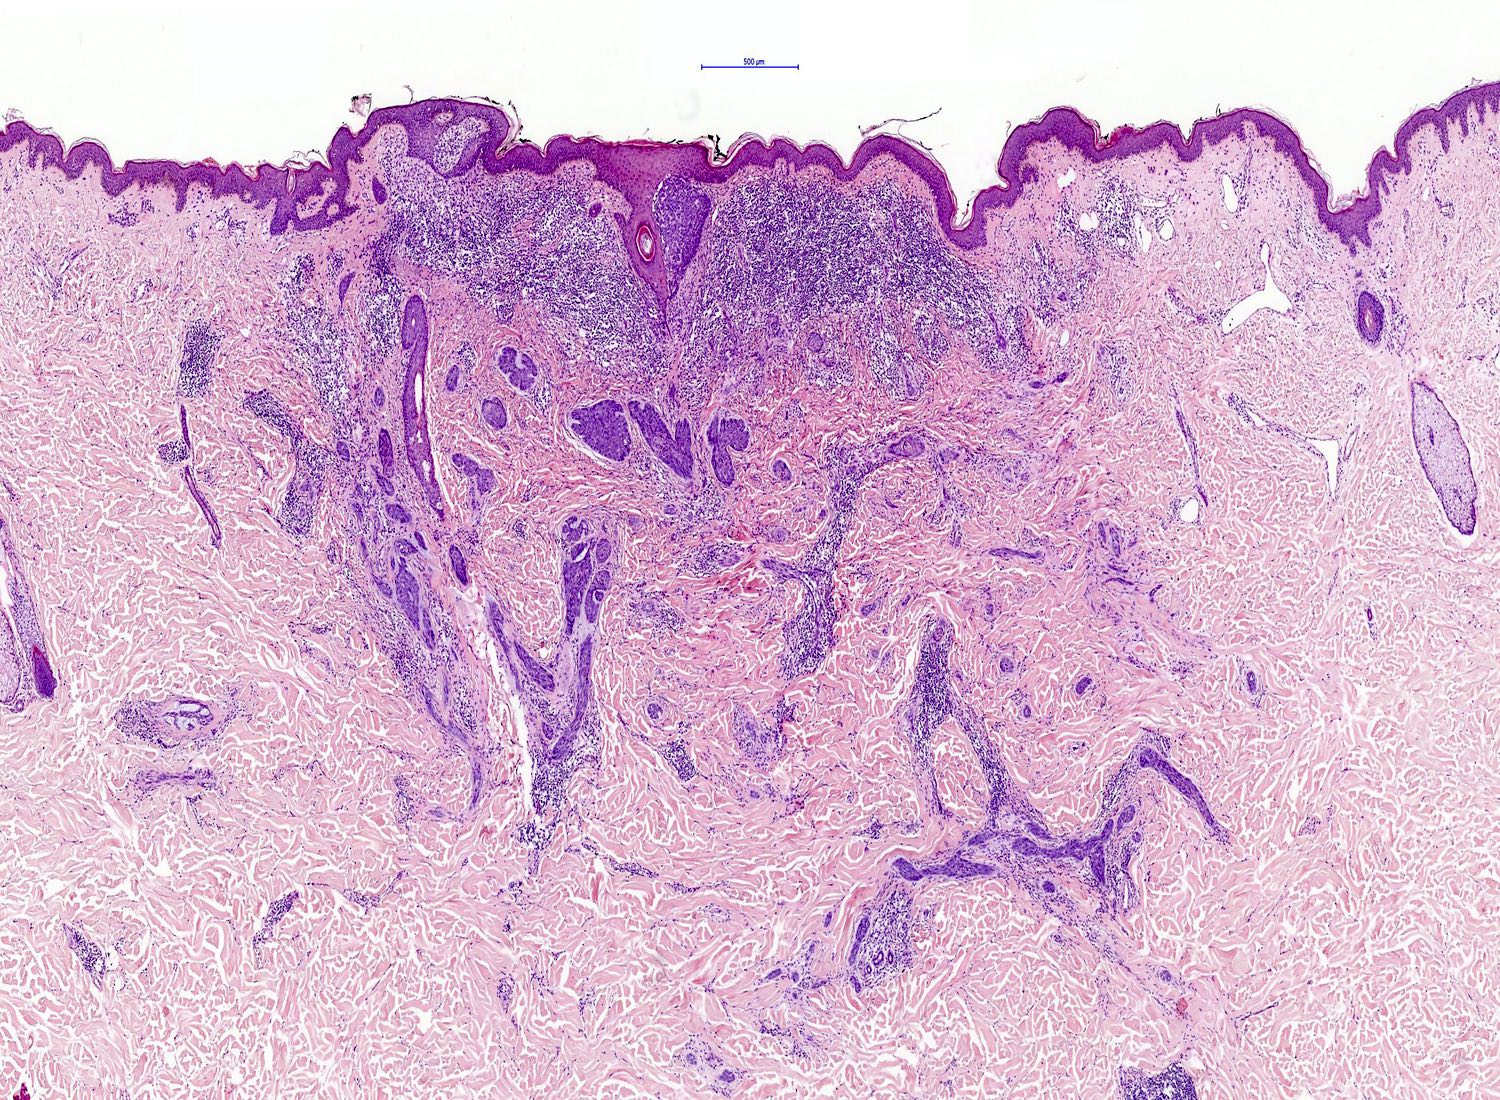

- Infiltrative BCC

- Small irregular clumps of basaloid cells

- Limited peripheral palisading

- Stroma loose and mucin may be prominent

- Extensive spread

- Perineural invasion can be seen

Microscopic (histologic) images

Contributed by Antonina Kalmykova, M.D., Phillip H. McKee, M.D., Sate Hamza, M.D., Eduardo Calonje, M.D.,

Wayne Grayson, M.B.Ch.B., Ph.D., James Sampson, M.B.B.S., M.Sc. and Assia Bassarova, M.D., Ph.D.